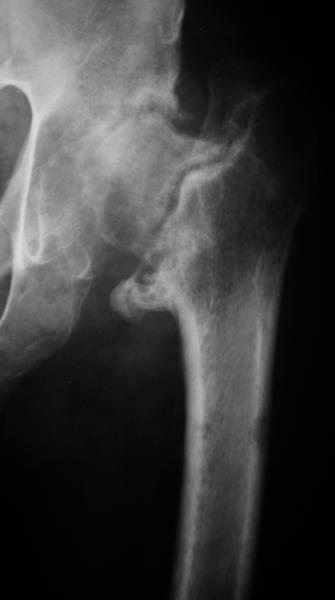

мужчина 55 лет, 1 год назад перелом шейки бедра. Лечился по месту

жительства в АВФ. Перелом несросся. Сейчас ходит с большим трудом,

опираясь на стул. На ногу не наступает. Укорочение 8 см. Иногда

беспокоит боль в паху.